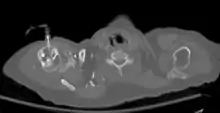

The needle is injected through the bone's hard cortex and into the soft marrow interior which allows immediate access to the vascular system. The IO needle is positioned at a 90 degree angle to the injection site, and the needle is advanced through manual traction, impact driven force, or power driven.[8] Each IO device has different designated insertion locations. The most common site of insertion is the antero-medial aspect of the upper, proximal tibia as it lies just under the skin and is easily located. This is on the upper and inner portion of the tibia. Other insertion sites include the anterior aspect of the femur, the superior iliac crest, proximal humerus, proximal tibia, distal tibia, sternum (manubrium).[9]